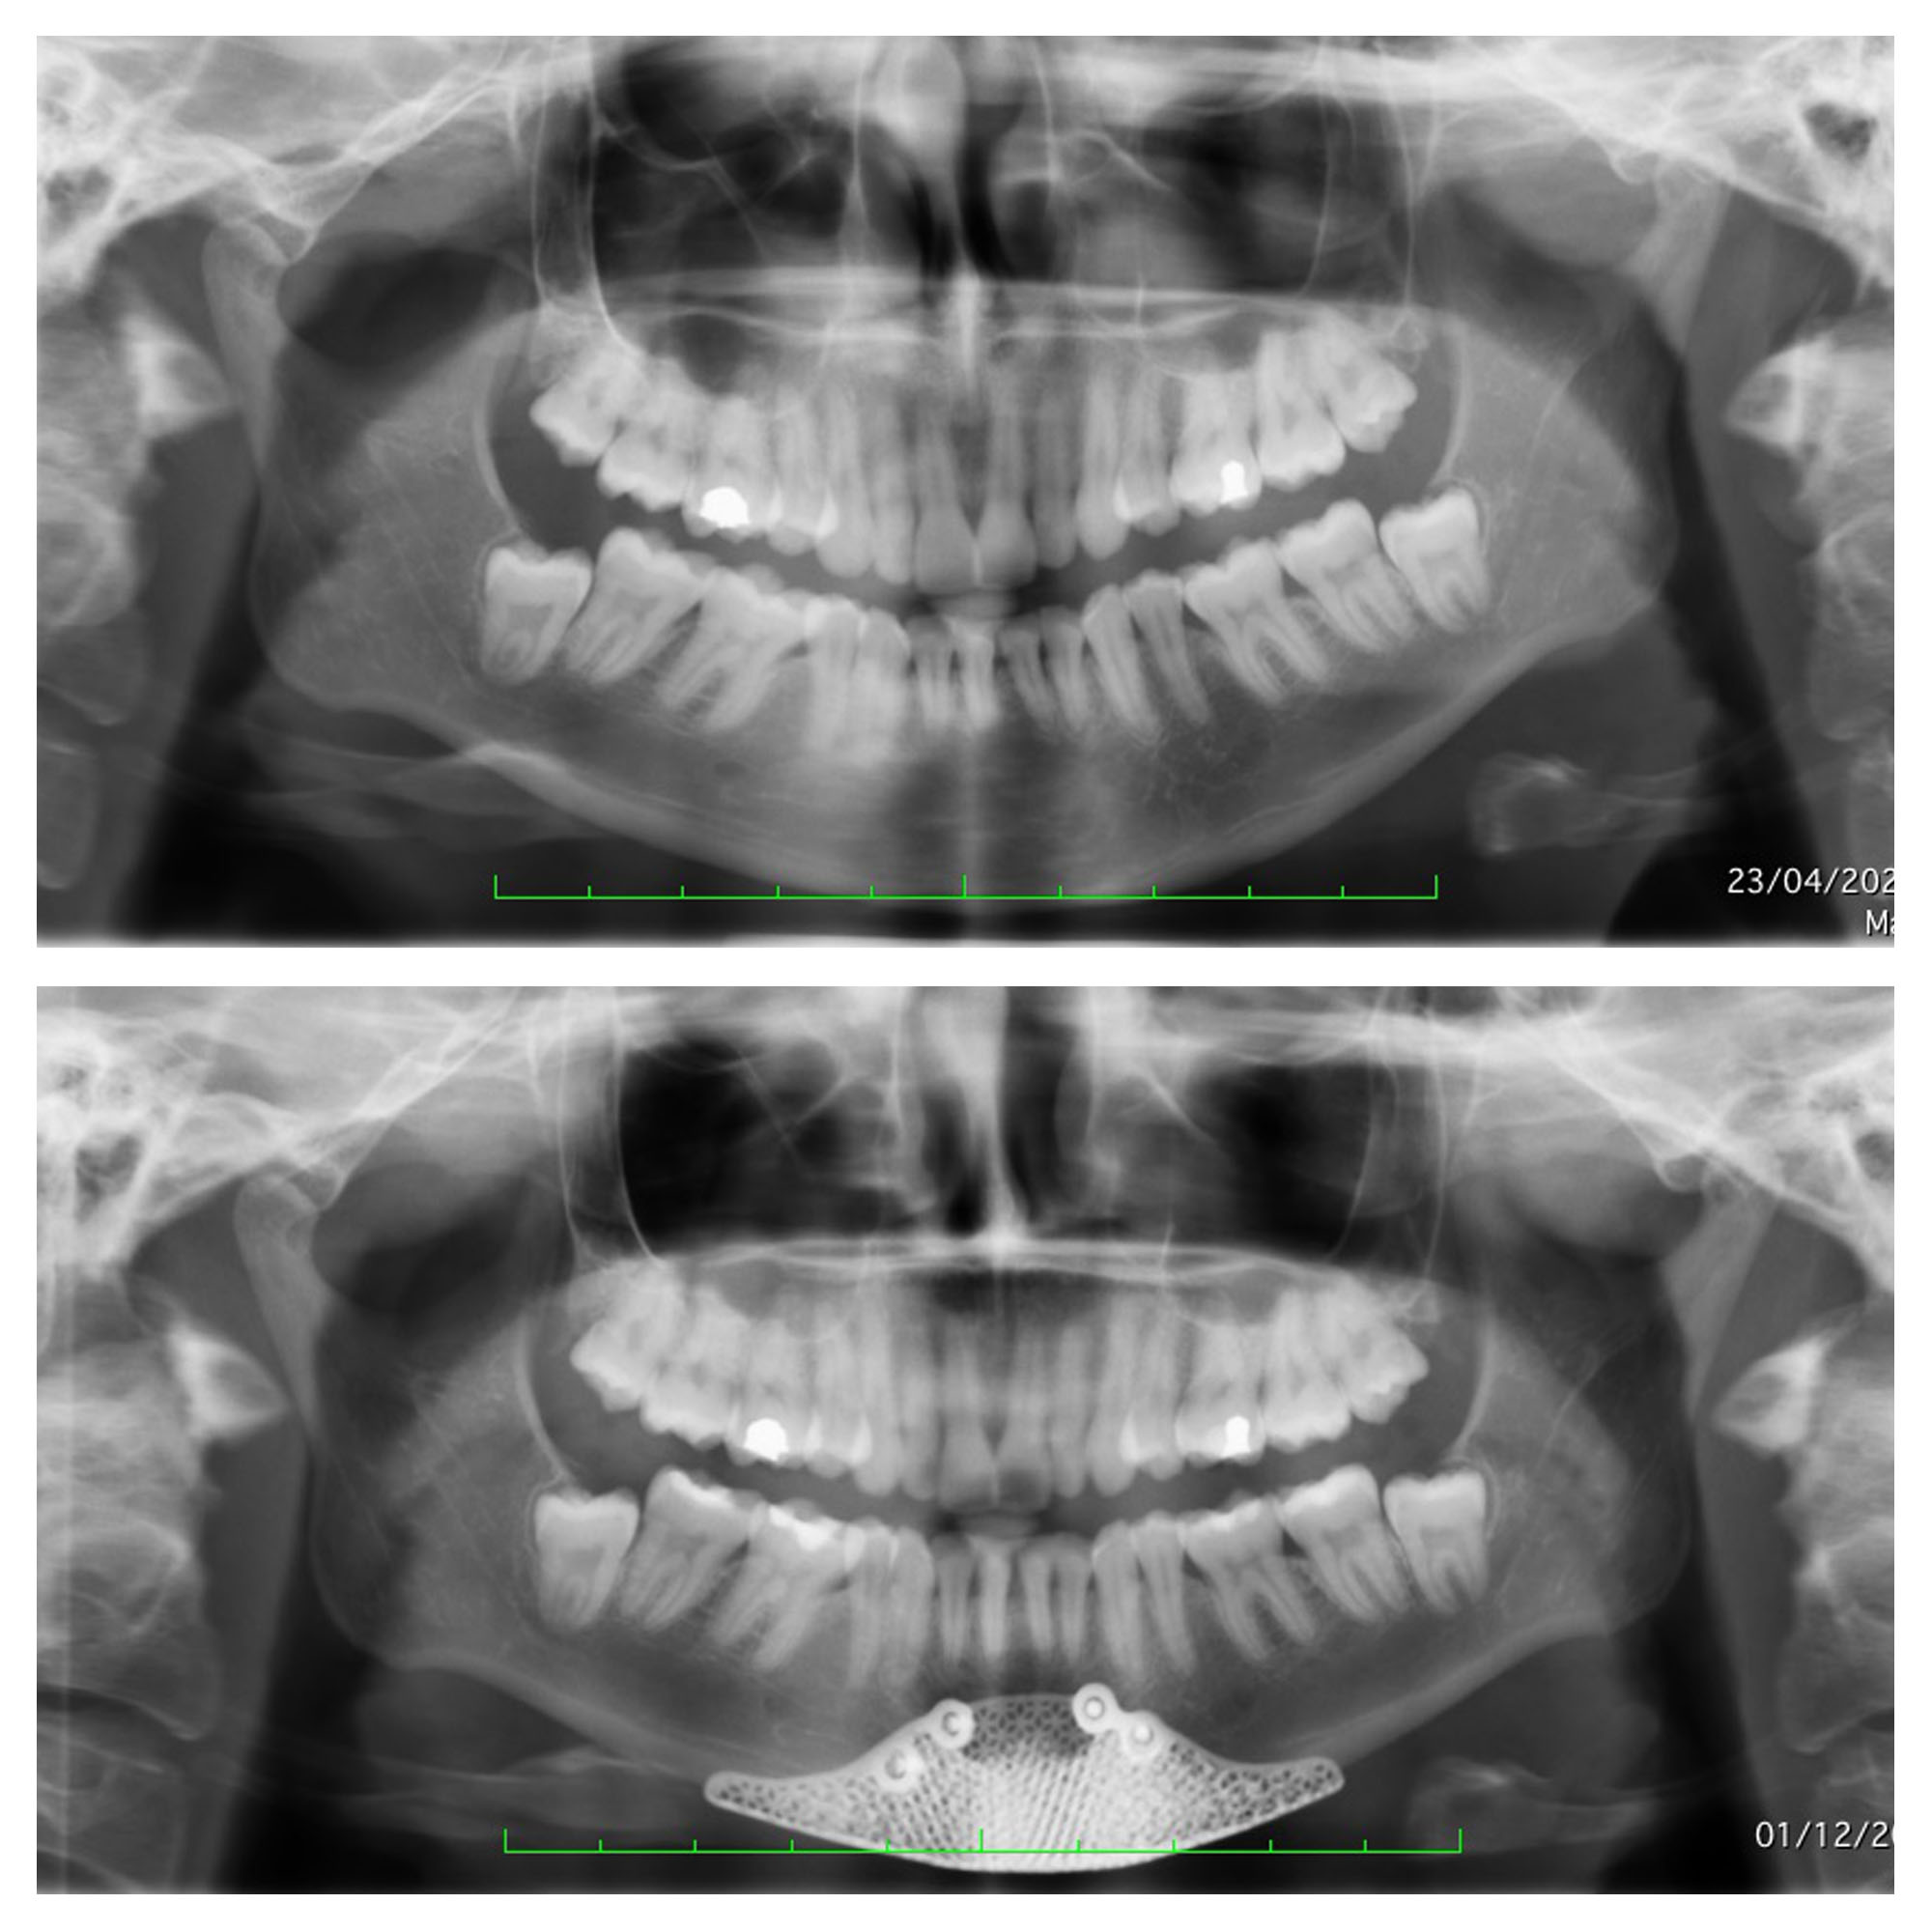

Comme on l’observe sur les radiographies ci-dessous, la chirurgie du menton osseuse permet de fixer avec une grande précision l’os du menton et d’utiliser cette opération pour obtenir un résultat d’une parfaite stabilité dans le temps, avec un potentiel esthétique très important. Pour plus d’informations sur les techniques de chirurgie du menton, vous pouvez consulter notre page sur la génioplastie paris.

radios génioplastie Paris

Voici un patient qui avait un menton trop long. La génioplastie a permis de réduire la hauteur tout en conservant une légère avancée esthétique.